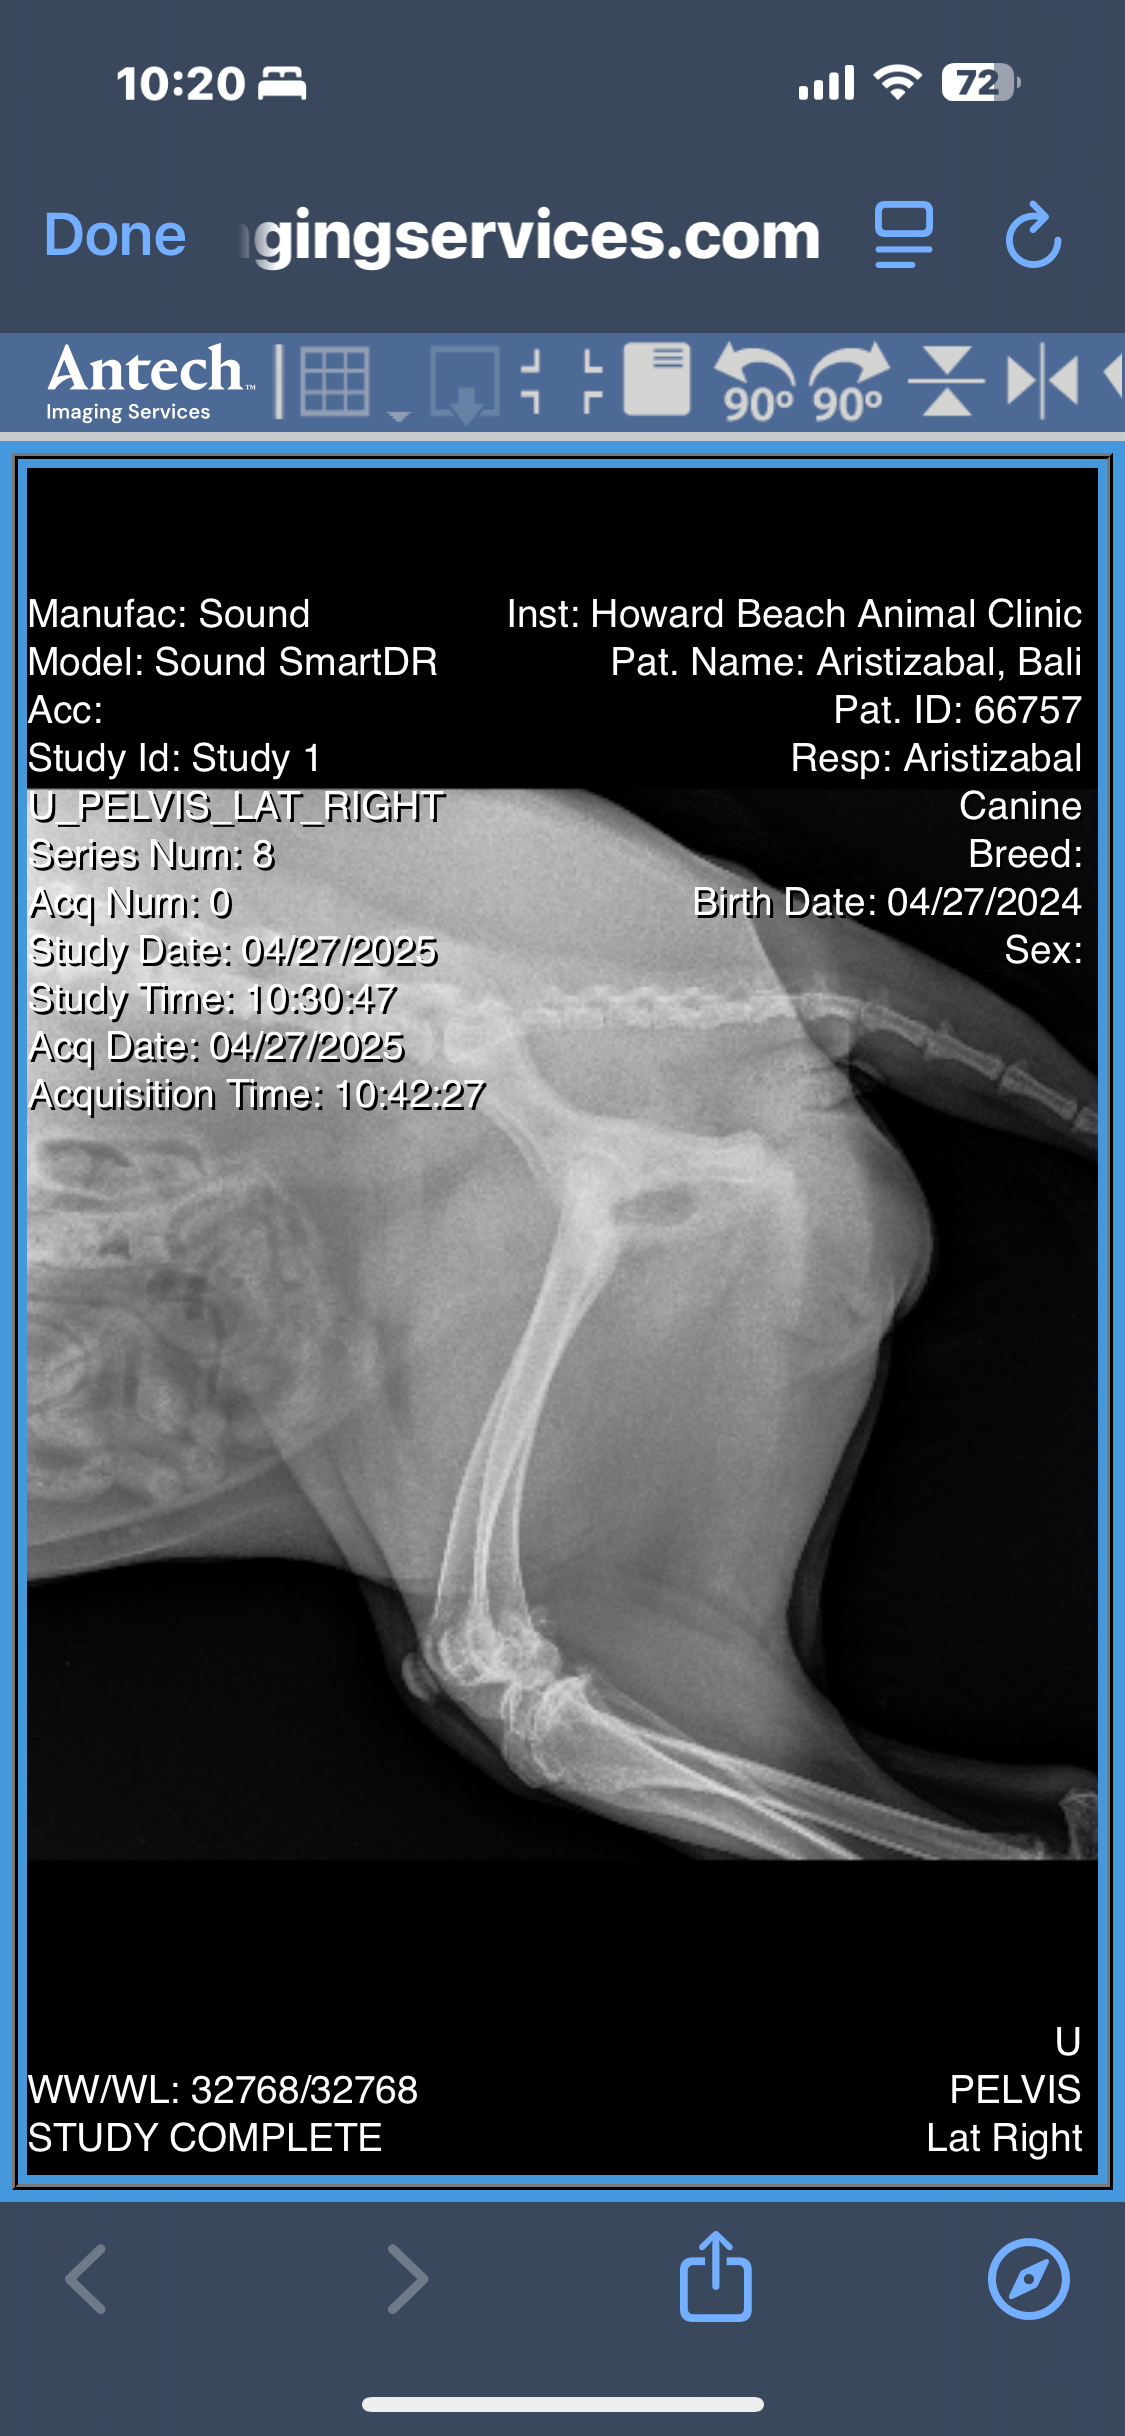

After months of limping, discomfort, and visits to the vet, Bali’s radiographs revealed multiple orthopedic issues:

• A minimally displaced fracture in her left femoral neck

• Severe bilateral hip dysplasia, more advanced on the left

• Osteoarthritis in both hips, with significant muscle atrophy

• Possible avascular necrosis of the femoral head or slipped femoral capital epiphysis

• And the concern of an underlying septic arthritis that hasn’t yet been ruled out